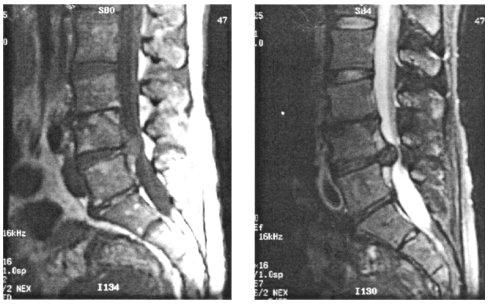

65 47 歲女性,主訴下肢神經症狀,其腰椎磁振造影(MRI)檢查,發現在第四,五節腰椎間後方出現 異常(圖左為 T1W 影像,圖右為 T2W 影像),最有可能的診斷為:

(A)腦膜瘤(Meningioma) (B)神經瘤(Neurogenic tumor) (C)椎間盤凸出(Herniated intervertebral disc) (D)感染性脊椎炎(Infectious spondylitis)